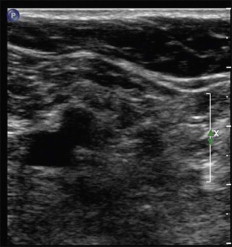

The study of the deep venous system is best performed with the patient supine, and with the hip rotated slightly outward. Begin with an anatomic survey in cross-sectional imaging with a transverse orientation of the transducer (described as the transducer rotated 90°). Identify the common femoral vein (CFV) at the level of the groin crease. Immediately adjacent to the CFV is the common femoral artery (CFA) ( Fig. 4.2 ). The arterial structures are an important deep venous ultrasound landmark for the examiner. The two vessels should be relatively equal in caliber and echogenicity. Marked vessel disparity may suggest aneurysmal dilatation, and the relevance of this finding will correspondingly have significance to either vessel. Additionally, identify the presence of any echogenic foci either within the vein ( Fig. 4.3A,B ) or the artery ( Fig. 4.4A,B ). Echogenicity within the vessel lumen are considered abnormal findings either as thrombus (venous) or atherosclerosis (arterial). With the patient relaxed, compression with the transducer at the skin’s surface should achieve complete coaption of the vein walls ( Fig. 4.5 ). The arterial structures do not collapse. The compression study is a careful full-length survey of the deep venous system and includes the common femoral (CFV), femoral (FV), deep femoral (DFV), popliteal (POP), posterior tibial (PTV), anterior tibial (ATV) and peroneal veins (PERO). This portion of the study should not be rushed, as there are variations to the anatomy. Compression and coaption of the veins is the mainstay of excluding deep vein thrombosis. Areas of venous noncompressibility suggest thrombosis within the lumen.